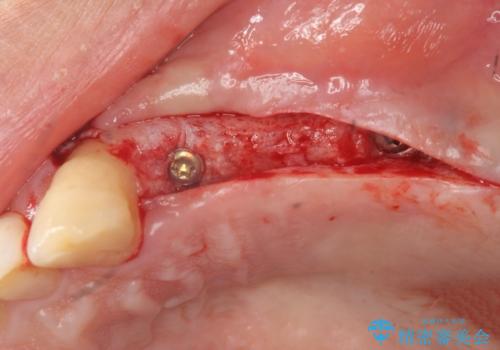

- 重度の虫歯により左上の歯を失い、インプラント治療は怖いため嫌厭して放置していたが、いよいよ食事に困りしっかりと噛めるようになりたいと希望され来院されました。

残存している小臼歯も虫歯が大きく保存が難しいため抜去を行い造骨を含めたインプラント治療を行います。

しっかりと造骨を行ったことでインプラント周囲には十分な量の骨が存在し安定したインプラント周囲環境を整えることができました。